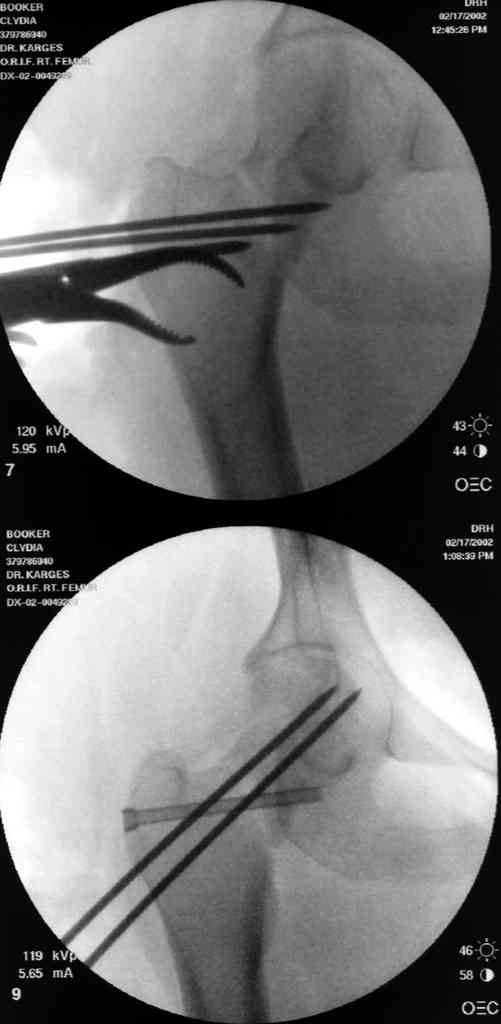

№2-3 типичная ошибка несоблюдения концепции параллельности шурупов, нарушение-фиксация поперечным допольнительным шурупом для приближения отломка в результате не сработало метод параллельных шурупов

№4 результат на КТ